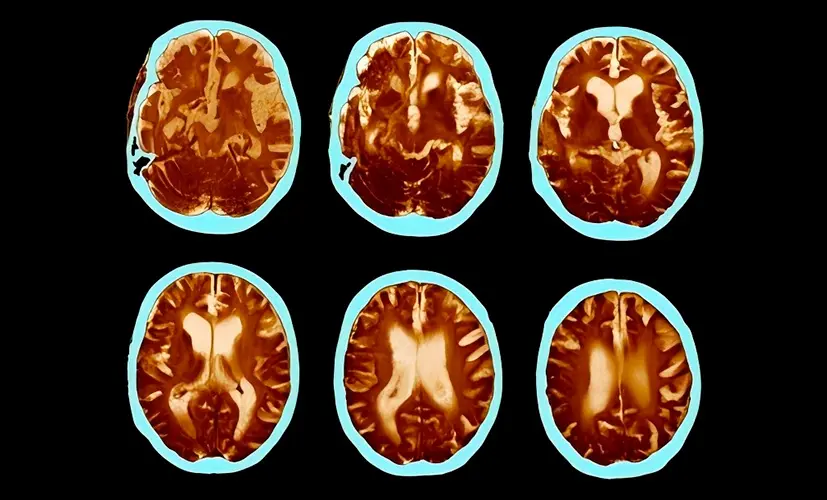

2. Dementia - the silent thief

Untreated cognitive decline can evolve into dementia. It may start as occasional forgetfulness, but before you know it, the condition has spread, impairing judgment and daily function. Patients describe the mental haze as a fog they can't escape. Most are diagnosed too late-when little more can be done.

4. Stroke caused by impaired blood flow